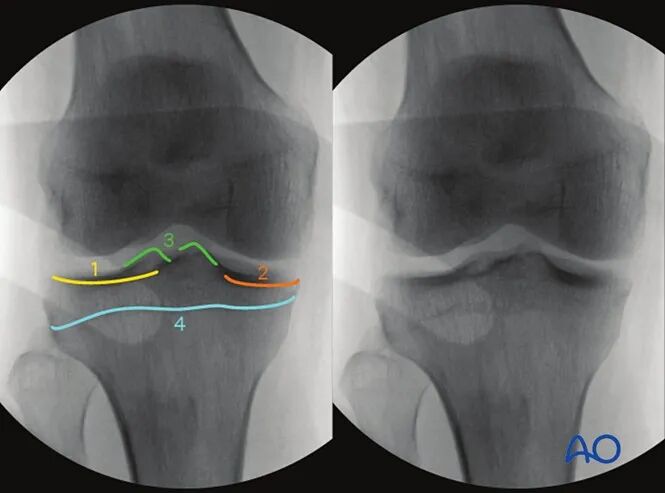

4. 胫骨近端10°头倾前后位

最佳体位摆放要求

以标准前后位为基础体位,

将C臂机向尾侧倾斜,直至清晰显示胫骨真实关节面,倾斜角度约为10°。

最佳影像的验证标准

满足以下条件即为胫骨真实关节面的最佳影像:

●胫骨关节面居中显示于影像屏幕;

●内侧与外侧关节面线影完全重合。

可识别的解剖标志与线条

该体位下可识别的解剖标志与线条包括:

1.外侧胫骨平台(凸面线影)

2.内侧胫骨平台(凹面线影)

3.内外侧胫骨棘

4.骨骺线瘢痕。

临床观察要点

该体位尤其适用于判断以下情况:

●关节面复位不良;

●关节内植入物位置;

●关节面与胫骨长轴的夹角是否正常(正常范围85°-90°)。